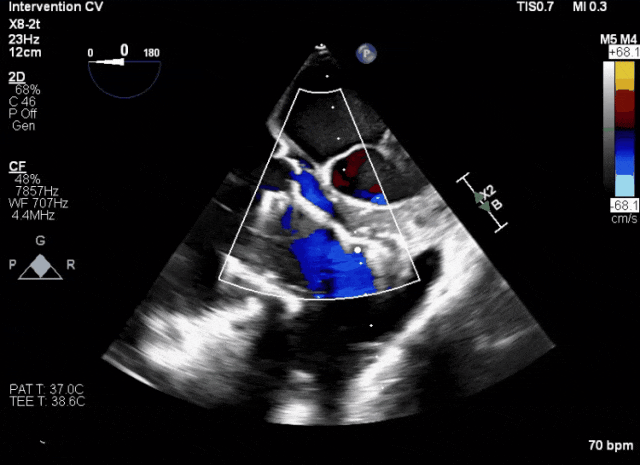

術后超聲顯示人工瓣膜穩定性良好,瓣葉啟閉正常

術后DSA、超聲顯示人工瓣膜穩定性良好,瓣葉啟閉正常,無瓣周漏

術后超聲評估瓣膜穩定性良好,無瓣周漏